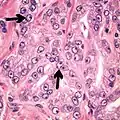

- Relatively common and highly specific

- [4]

- Multiple nucleoli

- Eccentric nucleoli[4]

Acinar adenocarcinoma with multiple nucleoli.

Acinar adenocarcinoma with double and eccentric nucleoli.